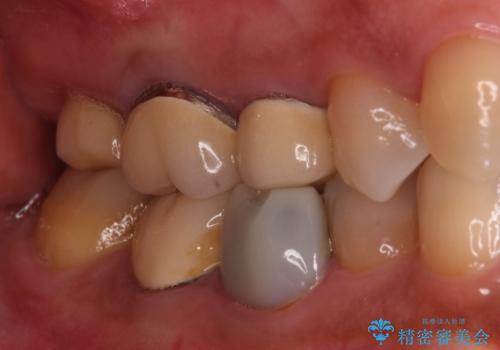

右上の一番奥の歯が欠損しており、その手前の歯2つを土台に連結されたクラウンが装着されていました。

不安定な咬み合わせとなっており、クラウンの表面が剥離していたため、インプラントによる欠損補綴治療を行い、手前2つの歯も一緒に補綴治療を行うこととしました。

治療中の仮歯も頻繁に壊れておりましたが、インプラントの土台が歯肉上に出てからは咬み合わせが安定し、仮歯が壊れることもなくなりました。